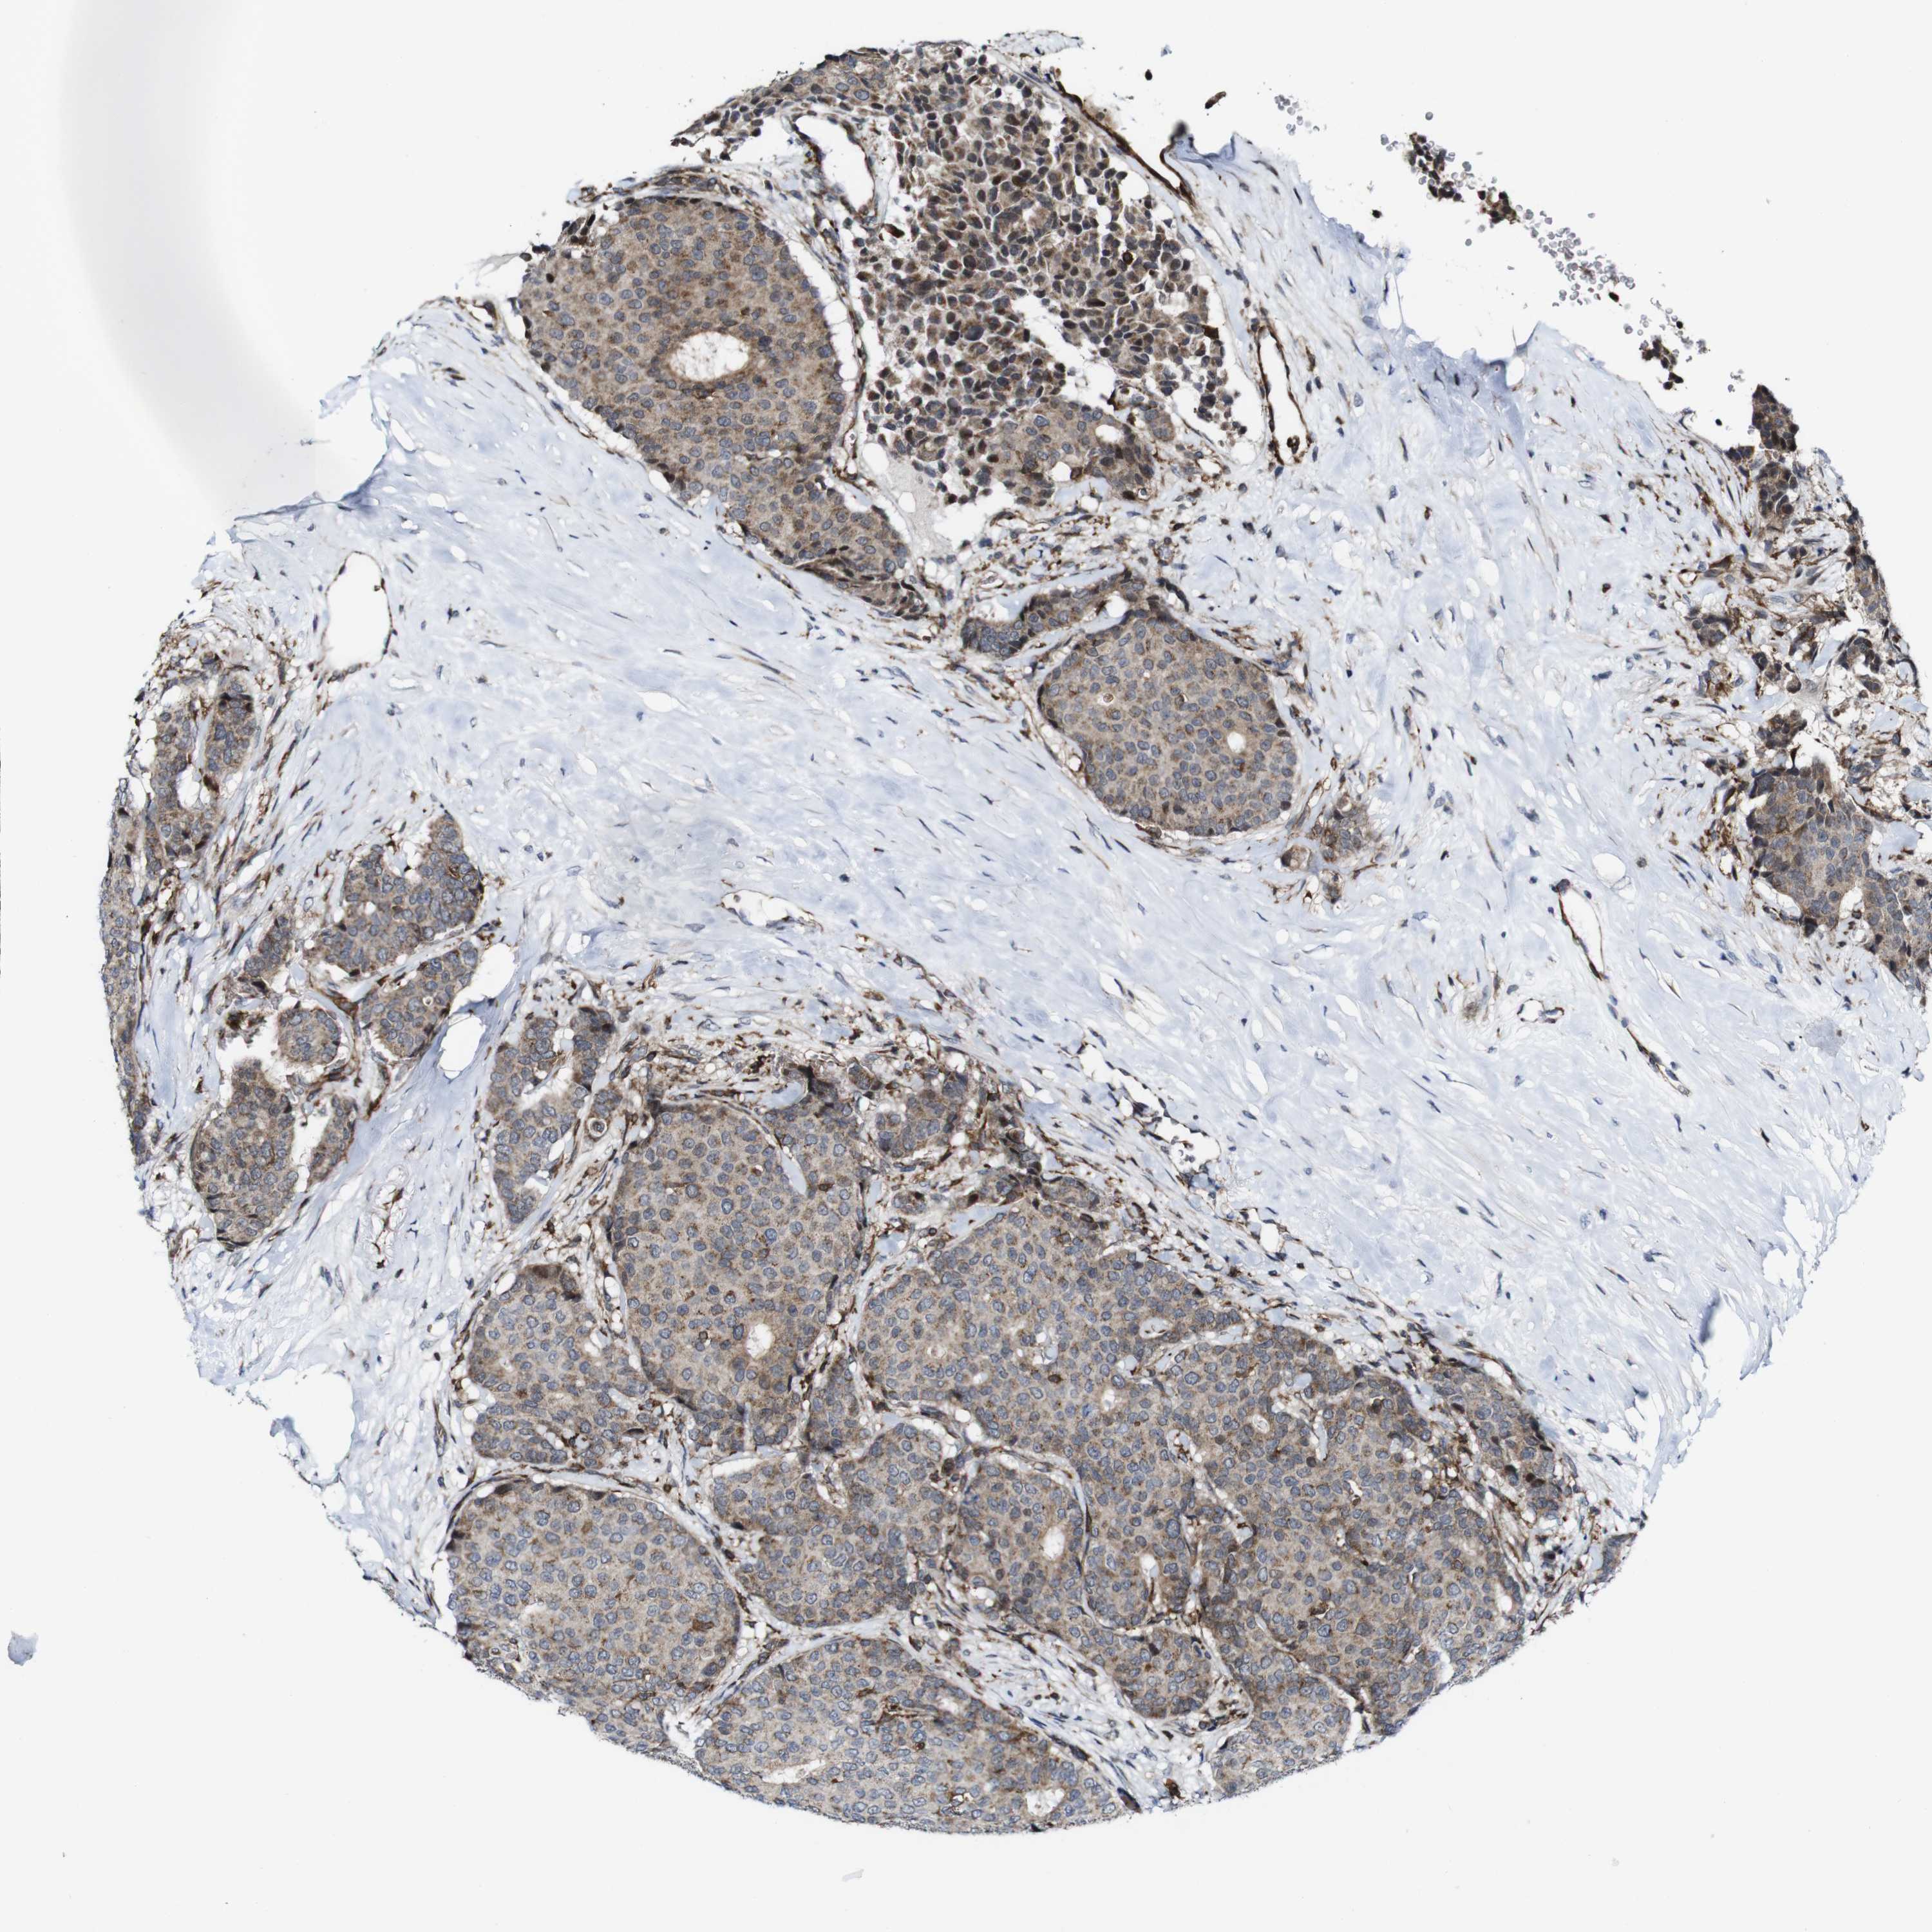

CANCER BREAST CANCER Show tissue menu

BRCA TCGA BRCA VALIDATION PROTEIN EXPRESSION

ANTIBODIES

AND

VALIDATION